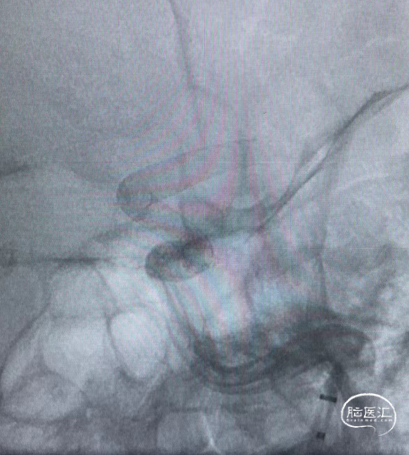

病例2

左侧颈内动脉眼动脉段动脉瘤

术前影像

术后影像

术后6个月随访完全栓塞

术后12个月随访完全栓塞

诊断:左侧颈内动脉眼动脉段动脉瘤,动脉瘤瘤体直径12.8mm,瘤颈直径6.5mm,载瘤动脉远端直径3.3mm,近端直径3.5mm;密网支架落脚于近端较为平直段血管处,直径略大。

处理策略:弹簧圈1枚,1枚如意SM*FDD-425-25mm治疗。